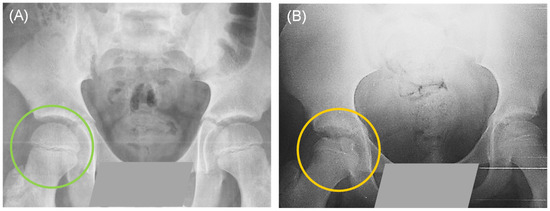

Some patients were first-time consultations and others recurrent; however, the clinical diagnosis described by the Pediatric Orthopedics Service indicated that all patients presented early stages of necrosis and fragmentation. Figure 1 shows a control individual and a patient with a clinical diagnosis of LCPD. Three patients presented bilateral involvement: in five of them, the affected limb was the right one, and in fifteen, the left one. During clinical interviews, some of the patients described relevant data; for example, most of the patients indicated the practice of some extreme sport, such as gymnastics, taekwondo, or soccer/football. Around 65% of our patients had pes planus, which has been linked to elevated stress loading of the hip. In addition, approximately 91% of our patient population reported having been exposed to maternal prenatal smoking and/or passive exposure to tobacco smoke, since one or both parents, or a close relative were smokers (Figure 2).

Figure 1. Simple pelvic X-ray in anteroposterior projection: (A) The green circle shows the intact femoral head of a healthy control. (B) The yellow circle shows a fragmented femoral head of a patient with Legg-Calvé-Perthes disease (LCPD).